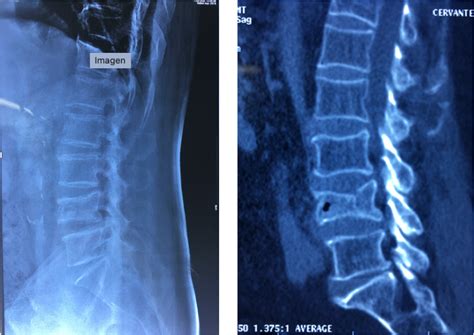

Osteoporosis En La Columna Lumbar, , , , , , , 0, Osteoporosis: Diagnosis, Prevention, & Management - Athletico, www.athletico.com, 2294 x 2056, jpeg, Weblaosteoporosis designa una patología ósea caracterizada por una reducción de la masa ósea que conduce a una alteración de la microarquitectura del tejido óseo. Los. WebLa osteoporosis es una enfermedad que afecta a las personas reduciendo la densidad de la masa ósea. Por ello, los huesos se vuelven más frágiles y menos resistentes a los., 20, osteoporosis-en-la-columna-lumbar, Novedades y Muebles Weblaosteoporosis designa una patología ósea caracterizada por una reducción de la masa ósea que conduce a una alteración de la microarquitectura del tejido óseo. Los. WebLa osteoporosis es una enfermedad que afecta a las personas reduciendo la densidad de la masa ósea. Por ello, los huesos se vuelven más frágiles y menos resistentes a los.

WebLa osteoartritis en la columna vertebral se divide anatómicamente en: Osteoartritis de la parte inferior de la espalda (columna lumbar), a veces llamada artritis lumbosacra, que. WebLa columna vertebral está compuesta de pequeños huesos llamados vértebras y las personas con osteoporosis generalmente se rompen los huesos de la parte. WebSe considera que la osteoporosis es una enfermedad propia de las mujeres posmenopáusicas. Sin embargo, los estudios epidemiológicos ponen de manifiesto que. WebLa osteoporosis es una enfermedad que se caracteriza por una disminución de la densidad de los huesos a causa de la pérdida del tejido óseo normal. Esto conlleva una. WebUna causa común del dolor lumbar es la estenosis de la columna lumbar. A medida que envejecemos, nuestra columna vertebral cambia. Estos efectos del uso y desgaste. Weblaosteoporosis Es una enfermedad esquelética difusa caracterizada por disminución de la masa ósea y una deterioro de la microarquitectura del tejido óseo. Es responsable de la. WebLa osteoporosis es una enfermedad que adelgaza y debilita los huesos. Sus huesos se vuelven frágiles y se quiebran fácilmente, especialmente los de la cadera,.